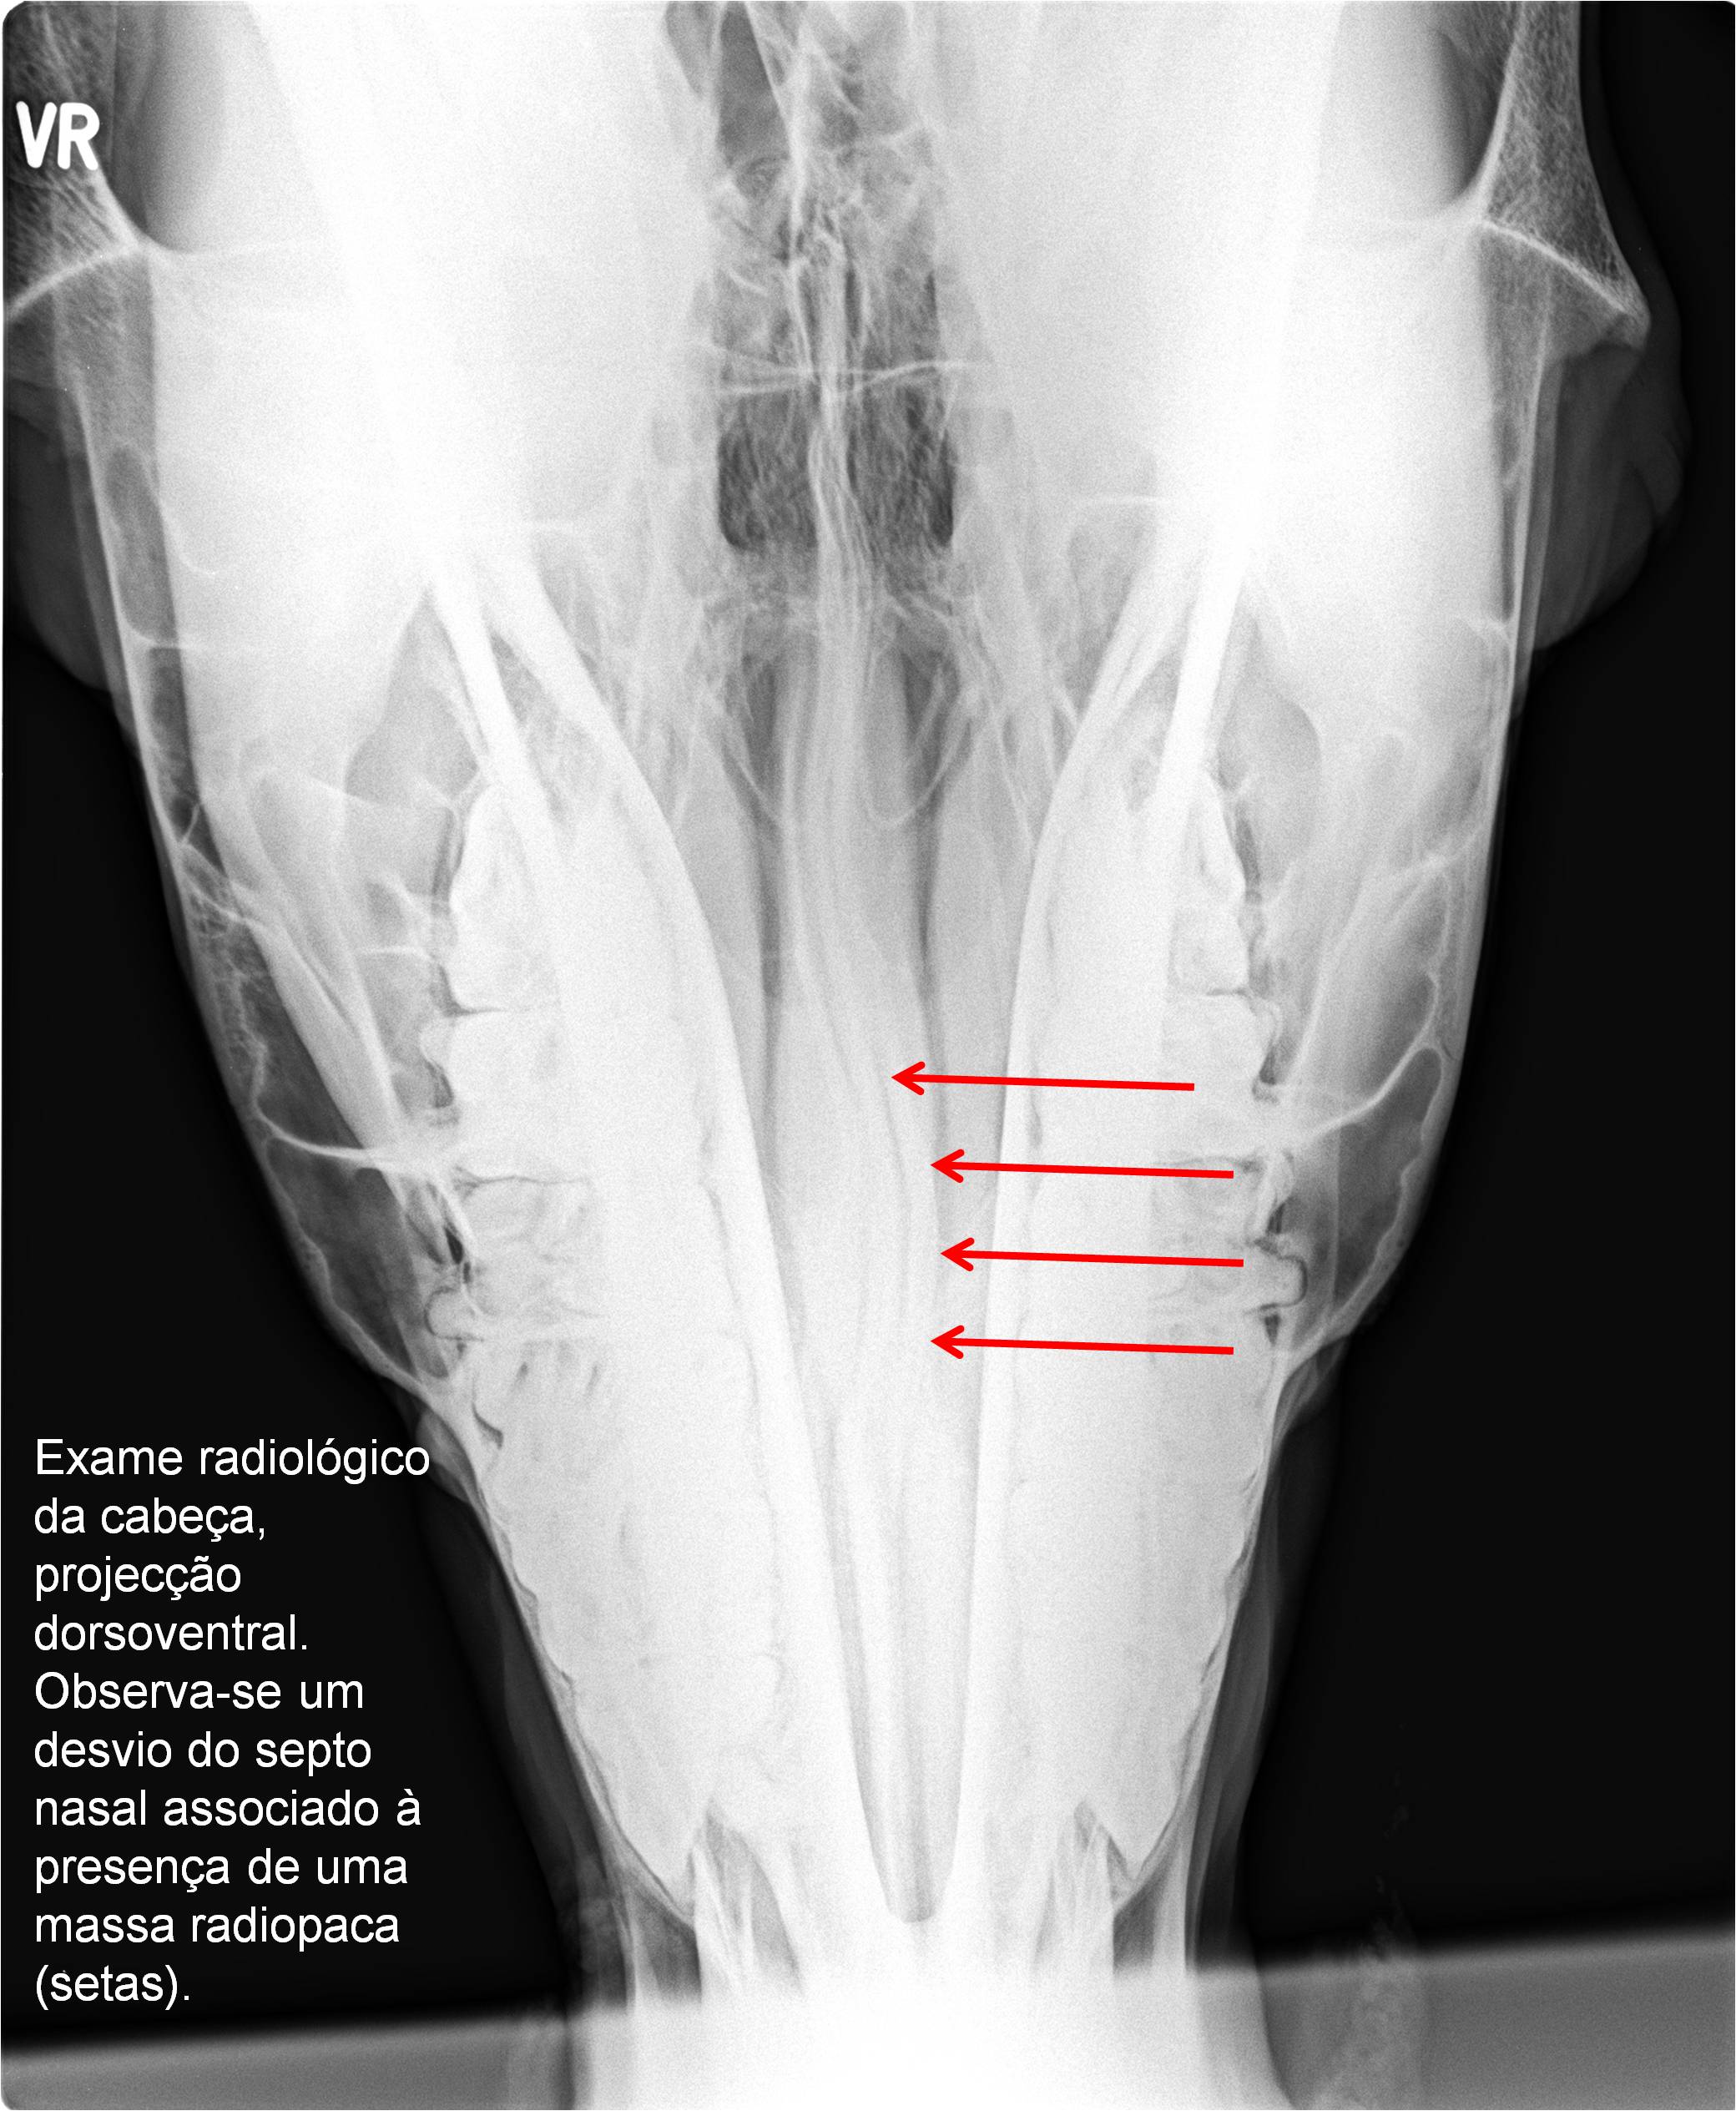

Publisher: Universidade de Évora

Abstract: O relatório de estágio encontra-se estruturado em três partes distintas. A primeira parte faz a caracterização das infraestruturas e funcionamento do Hospital Veterinário de Equinos de Lüsche, Oldenburg, Alemanha, assim como a análise casuística dos casos clínicos acompanhados durante os 6 meses de estágio. A segunda parte consiste de uma revisão bibliográfica sobre quistos do osso subcondral em equinos. Por fim, a terceira parte consta da apresentação e discussão de um caso clínico, nomeadamente o diagnóstico e acompanhamento imagiológico, por ressonância magnética, de um quisto subcondral na terceira falange num cavalo adulto; ### Abstract Equine Practice- Subcondral bone cyst of the third phalanx This internship report is divided in three parts. The first part characterizes the infrastructure and function of the Equine Hospital Lüsche, Oldenburg, Germany, as well as the casuistic of the clinical cases accompanied during the 6 month internship. The second part consists in a bibliographic review of cystic lesions of the subchondral bone in equines. The third part consists in a case report, the diagnostic and imagiological accompaniment, by use of magnetic resonance imaging, of a subchondral bone cyst in the distal phalanx of an adult equine.